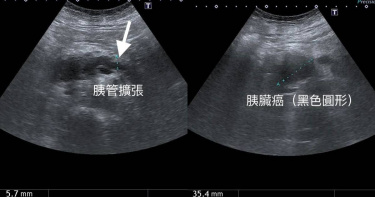

她胃痛全身超癢⋯皮膚變黃「尿出烏龍茶色」 醫一看:狡猾「癌王」

有「癌王」之稱的胰臟癌因早期沒有明顯表徵,等到發現時,情況往往已無法挽回。一名女病患一直以為胃痛是因為胃病復發,直到近日皮膚變黃、全身發癢,加上小便呈烏龍茶顏色,因此到醫院就醫,結果一照超音波,發現胰臟的頭部有一個深黑色3.5公分的腫瘤。醫師錢政弘在粉專《錢政弘 胃腸肝膽科醫師》分享一則案例,一名60多歲的女病患因為皮膚變黃來急診就醫,而在一年多前,女病患就曾因胃痛做過胃鏡檢查,當時發現有胃潰瘍,因此吃了一段時間的潰瘍藥;不過藥吃完沒多久,女病患發現胃又開始隱隱作痛,以為是胃病沒好,因此到家裡附近診所拿藥吃,然而胃痛都沒有明顯改善。女病患透露,整天上腹部都隱隱作痛,有沒有吃東西都一樣,不會劇痛,但食量越來越小,吃不到半碗飯,且最近10天發覺全身越來越癢,小便甚至變成烏龍茶的顏色,至於大便的顏色則是淡黃色。錢政弘聽完症狀後,研判膽管有嚴重的阻塞造成黃疸,癌症引起的可能性最大。果然一照超音波,發現胰臟的頭部有一個深黑色3.5公分的腫瘤,胰臟的胰管也擴張到5.7公釐,肝臟內外的膽管都明顯的擴張。錢政弘直言,應該就是胰臟癌了。錢政弘指出,胰臟癌相當狡猾。(圖/翻攝自臉書/錢政弘 胃腸肝膽科醫師)錢政弘解釋,長在胰臟頭部的腫瘤會堵住膽管和胰管,造成消化酶(脂肪酶)無法進入十二指腸,可能導致大便會有浮油出現,但這位女病患表示沒有脂肪便或是背痛,一直以為腹部隱隱作痛是胃痛,想吃胃藥緩解,直到體重減輕和全身發癢 ,才發覺不對勁。錢政弘指出,胰臟癌相當狡猾,因此提供胰臟癌在胰臟的不同部位出現的症狀供大家參考。1.頭頸部:體重減輕、黃疸、膽管炎、飯後疼痛、腹脹、脂肪便。2.體部:上腹痛或背痛。3.尾部:上腹痛或背痛,轉移部位疼痛。